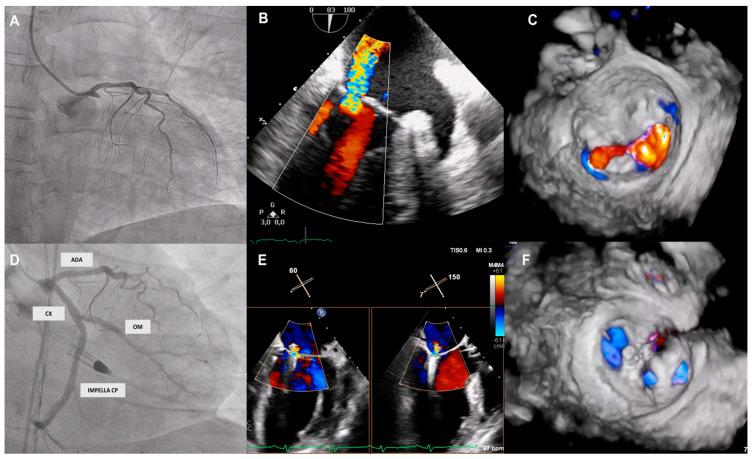

Patients with cardiogenic shock (CS) and mitral regurgitation (MI) have a prohibitive risk that contraindicates surgical treatment. Although the feasibility of transcatheter edge-to-edge therapy (TEER) has been demonstrated in this setting, the benefit of the combined use of TEER with mechanical circulatory support devices (MCS) has not been studied. The aim of this study was to evaluate the clinical outcomes of TEER in patients with MCS. The MITRA-ASSIST study is a retrospective multicentre Spanish registry that included patients with MR and CS who underwent TEER in combination with MCS. The primary endpoint was death from any cause at 12 months. The secondary endpoint was a composite of death from any cause or hospitalisation for heart failure at 12 months. A total of twenty-four patients in nine high-volume Spanish centres (66.2 (51-82) years, 70.8% female, EuroSCORE II 20.4 ± 17.8) were included. Acute ST-elevation myocardial infarction was the main CS aetiology (56%), and the most implanted MCS was the intra-aortic balloon pump (82.6%), followed by ECMO (8.7%), IMPELLACP (4.3%), or a combination of both (4.3%). Procedural success was 95.8%, with 87.5% in-hospital survival. At 12-month follow-up, 25.0% of patients died, and 33.3% had a composite event of death from any cause or hospitalisation for heart failure. TEER in patients with concomitant CS and MR who require MCS appears to be a promising therapeutic alternative with a high device procedural success rate and acceptable mortality and heart failure readmission rates at follow-up.

心源性休克(CS)和二尖瓣反流(MI)患者面临的风险极高,禁忌进行手术治疗。尽管经导管缘对缘治疗(TEER)在这种情况下的可行性已得到证实,但TEER与机械循环支持设备(MCS)联合使用的益处尚未得到研究。本研究的目的是评估MCS患者接受TEER的临床结局。MITRA-ASSIST研究是一项回顾性多中心西班牙注册研究,纳入了接受TEER联合MCS治疗的MR和CS患者。主要终点是12个月时的任何原因死亡。次要终点是12个月时任何原因死亡或因心力衰竭住院的复合终点。西班牙9个高容量中心的24例患者(66.2(51 - 82)岁,70.8%为女性,欧洲心脏手术风险评估系统II评分为20.4±17.8)被纳入研究。急性ST段抬高型心肌梗死是CS的主要病因(56%),最常植入的MCS是主动脉内球囊泵(82.6%),其次是体外膜肺氧合(ECMO,8.7%)、IMPELLACP(4.3%)或两者联合使用(4.3%)。手术成功率为95.8%,住院生存率为87.5%。在12个月的随访中,25.0%的患者死亡,33.3%的患者发生了任何原因死亡或因心力衰竭住院的复合事件。对于需要MCS的CS和MR合并患者,TEER似乎是一种有前景的治疗选择,器械手术成功率高,随访时死亡率和心力衰竭再入院率可接受。